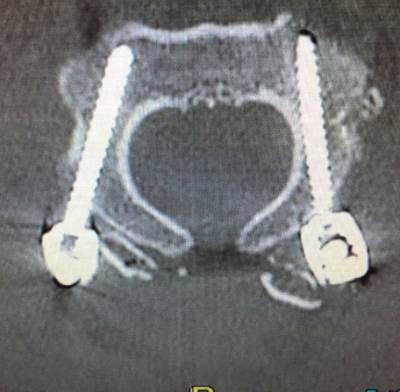

Atlantoaxial Instability TreatmentAtlantoaxial Instability TreatmentIn the Axis, pedicle screws are usually the first choice although, depending on the patient’s anatomy, placement of isthmic screws may be considered. Atlas’ screws are generally placed in the lateral masses. Atlas and axis screws are joined in each side by lateral bars that are unifying the instrumented fusion system. In most cases it is convenient to put bone graft, usually autologous, taken from the iliac crest or the patient’s own rib. In the cases where it is not possible to obtain autologous bone graft, heterologous graft (artificial bone) may also be used.

Atlantoaxial Instability Treatment 2Atlantoaxial Instability Treatment 2After the preoperative analysis of the Magnetic Resonance Imaging (MRI) and CT scan of each patient, we perform a thin sliced preoperative CT oriented towards neuronavigation that will be carried out during surgery. Prior to surgery we perform a surgical planning of the intraoperative neuronavigation to confirm the trajectories of screws and special anatomical dispositions of structures. It is also important to know and evaluate patients’ concomitant diseases or comorbidities which are frequent in patients affected by Ehler Danlos, such as POTS, Mast Activation Syndrome, cardiac abnormalities … etc. Knowing this it allows to anticipate any possible problems in the postoperative period.